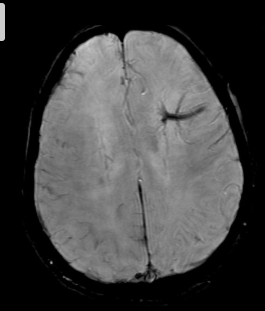

Como a embolia gordurosa se apresenta na imagem?

Multiplas pequenas lesões em padrão estrelado

Pontinhos pretos (SWI) ou hipersinal no FLAIR